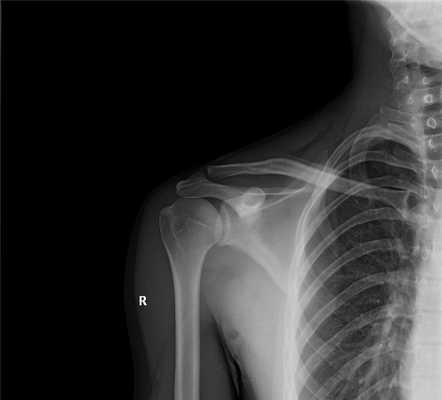

Рентген в двух проекциях (прямой и осевой) довольно чётко может показать отклонение текущего состояния плечевого сустава от нормы. На снимках можно увидеть, насколько смещена головка плечевой кости, каково направление её смещения, а также наличие переломов костей (если они есть). С помощью рентгена можно определить тип вывиха и предположить развитие возможных осложнений. Не допускается вправлять вывих без предварительного проведения рентгена.

Перелом шейки плечевой кости, боковой части лопатки или ключицы

Все кости на рентгене отображаются в виде плотных белых образований. Переломы костей, а также трещины на них выглядят на снимках как тёмные полосы, расположенные в различных направлениях и имеющие различную локализацию и размер. Фото-рентген плечевого сустава позволяет обнаружить наличие переломов плечевой кости, ключицы и лопатки. Снимок нужен для того, чтобы определить сложность перелома, увидеть, как расположены осколки костей (если имеет место раздробление).

СНИМОК ПЛЕЧЕВОГО СУСТАВА В АКСИАЛЬНОЙ ПРОЕКЦИИ

Назначение снимка. Снимок предназначен для отображения плечевого сустава в плоскости, перпендикулярной к фронтальной, в которой производятся снимки в прямой задней проекции. Снимок в аксиальной проекции дает возможность определить направление смещения головки плечевой кости при вывихе в плечевом суставе, а также характер смещения отломков при переломах проксимального отдела плечевой кости.